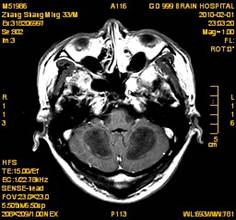

案例1 患者,男,33岁, 海洛因脑病的头颅MR。表现为双侧大脑后部皮层下白质、双侧内囊后肢、枕叶白质、胼胝体压部、中脑、桥脑、双侧小脑半球齿状核质及双侧桥臂多发对称性片状及斑片状长T1长T2异常信号影,FLAIR序列呈高信号,其中双侧内囊后肢表现为特异的“八字征”,双侧小脑半球齿状

核质表现为对称的“蝶翼征”,脑干病变呈“蟹钳征”及“中空征”。增强后双侧半卵圆中心、双侧枕叶白质及双侧小脑半球病变内或边缘中度强化影。给予患者抗炎、脱水、疏通血管及营养神经等药物治疗,一个月后痊愈出院。